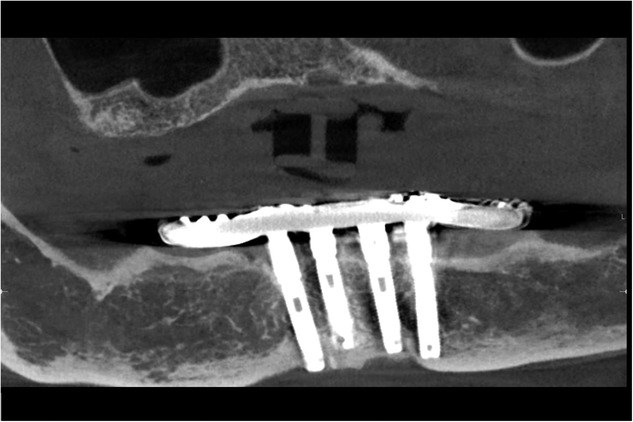

In the February issue of the Journal of Prosthodontics and online now, Dr. Thomas J. Balshi, Dr. Glenn J. Wolfinger, Mr. Stephen F. Balshi, and Dr. Avinash Bidra present a clinical report of a 30-year follow-up of an edentulous patient rehabilitated with only 4 implants.

The article also reviews the biologic and biomechanical response to this treatment protocol and points out the long-term clinical observations and prosthodontic maintenance related to this popular form of implant therapy.

There was no loss of any implants, and the bone levels around all implants were excellent, along with osteogenesis in the distal cantilever region, and there were no biologic complications. The prosthodontic framework was intact, but there was continued prosthodontic complication related to the wear and fracture of acrylic resin denture teeth, which underscores the importance of patient recall and professional maintenance to ensure the optimal performance of the prosthesis.